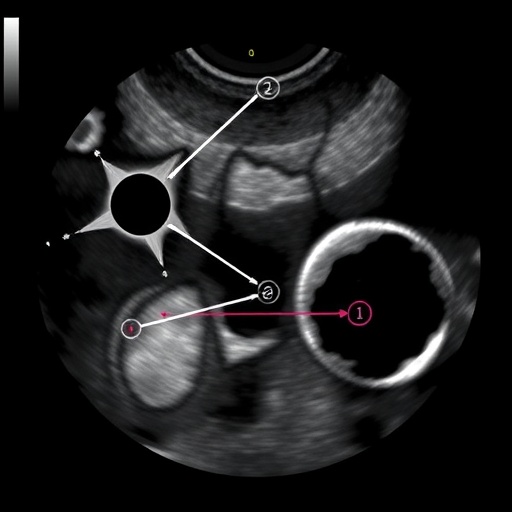

Ultrasound allows for the assessment of lymph nodes based on size, shape, echogenicity, and vascularity. For instance, characteristic features commonly observed in normal lymph nodes include an oval shape, a thin cortex, and a central echogenic area known as the hilum. In contrast, suspicious nodes may exhibit irregular borders, hypoechoic characteristics, and increased vascular flow. These nuanced differences are critical for radiologists and clinicians alike when determining the likelihood of neoplastic conditions versus reactive hyperplasia due to infection or inflammation.